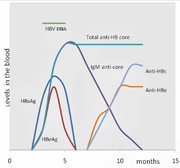

المضاد السطحي لالتهاب الكبد ب (HBsAg) هو الأكثر استخداما للكشف عن وجود هذا المرض. وهذا هو أول مضاد ڤيروسي يظهر خلال العدوى. ومع ذلك، في بداية الإصابة، قد لا يكون موجودا مضاد الڤيروس كما قد يكون غير مكتشف لاحقا من العدوى لأنها تتم إزالته من قبل المضيف. وتحتوى الفيريون المعدية على "الجسيمات الأساسية" داخلية التي تحتوى على الجينوم الڤيروسي. وتتكون الجسيمات الأساسية icosahedral من 180 أو 240 نسخة من البروتين الأساسي، والمعروف خيارياً باسم مضاد الالتهاب الكبدي البائي الأساسي، أو HBcAg. خلال هذه «النافذة» حيث لا يزال المضيف مصاب لكن يزيل الڤيروس بنجاح، والأجسام المضادة IgM لمضاد التهاب الكبد الوبائي ب الأساسي(anti-HBc IgM) قد يكون الدليل الوحيد المصلي للمرض.

بعد وقت قصير من ظهور HBsAg، يظهر مضاد آخر يدعى مضاد التهاب الكبد الوبائي ب e (HBeAg). تقليديا، فإن وجود HBeAg في مصل المضيف يرتبط بمعدلات أعلى بكثير من تكاثر الڤيروس والعدوى المعززة، ولكن لا تنتج المتغيرات من ڤيروس التهاب الكبد المضاد e، ولذلك فإن هذه القاعدة لا تنطبق دائما. خلال المسار الطبيعي للعدوى، قد يتم تطهير HBeAg، وتظهر الأجسام المضادة للمضاد e (anti-HBe) على الفور. ويتبع هذا التحويل عادة حدوث انخفاض هائل في تكاثر الڤيروس.

إذا كان المضيف قادر على التخلص من العدوى، يصبح HBsAg في النهاية غير مكتشف، ويليه IgG الأجسام المضادة للمضادات السطحية لالتهاب الكبد باء والمضادات الأساسية، (anti-HBs، anti HBc IgG).[9] الفترة الزمنية الفاصلة بين إزالة HBsAg وظهور anti-HBs تسمى فترة النافذة. ويعتبر الشخص السلبي لHBsAg لكن ايجابي anti-HBs إما أزال العدوى أو تم تطعيمه سابقا.

الأشخاص الذين يحتفظون بHBsAg إيجابي لستة أشهر على الأقل تعتبر حاملة لالتهاب الكبد باء.[23] وقد يكون حامل الڤيروس مصاب بالتهاب الكبد المزمن، والذي من شأنه أن ينعكس على مستويات مرتفعة من الانين امينوترانسفيراس في المصل والتهاب الكبد، كما يتبين من العينة الحية. أما حاملى المرض الذين ينتقلوا إلى حالة سلبية للHBeAg، لا سيما أولئك الذين اكتسبوا العدوى مثل البالغين، يكون بهم القليل جدا من تكاثر الڤيروس، وبالتالي قد يكون على قدر ضئيل من مخاطر حدوث مضاعفات على المدى الطويل أو لنقل العدوى إلى الآخرين.[24]

يعتبر فحص المستضد السطحي HBsAg هو الفحص الأكثر استعمالاً لتشخيص الإنتانات الحادة بڤيروس HBV وكشف الحملة. حيث يمكن كشفه باكراً منذ الأسبوع الأول أو الثاني وحتى الأسبوع 11- 12 من التعرض لڤيروس HBV، وذلك إذا استخدمت طرق مقايسة حساسة. يدل وجود HBsAg على أن الشخص معدٍ بغض النظر عن كون الإنتان حاداً أو مزمناً.

تتطور الأضداد اللبية Anti - HBc في كل إنتانات HBV، وهي تظهر بعد HBsAg بفترة قصيرة في المرض الحاد، و تدل على الإنتان بڤيروس HBV في وقت سابق غير محدد. تتطور هذه الأضداد بعد الإنتان بڤيروس HBV فقط، أي لا تتطور عند الأشخاص الذين لديهم مناعة لڤيروس HBV ناجمة عن التلقيح. تستمر الأضداد اللبية Anti - HBc بشكل عام مدى الحياة، وهي ليست واصمة مصلية للإنتان الحاد.

تظهر الأضداد اللبية من نوع IgM Anti - HBc) IgM) عند الأشخاص المصابين بمرض حاد عند بداية المرض تقريباً، وهي تشير لإنتان حديث بڤيروس HBV. تكون IgM Anti - HBc قابلة للكشف بصورة عامة بعد 4 - 6 أشهر من بداية المرض، وتعتبر الواصمة المصلية المفضلة للإنتان الحاد بڤيروس HBV. إن سلبية هذه الأضداد مع إيجابية فحص HBsAg في عينة دم واحدة يشير للانتان المزمن بڤيروس HBV.

إن HBeAg واصمة مفيدة، وتترافق بقوة مع عدد جزيئات HBV المعدية في المصل مع خطورة عالية لنقل العدوى (الإخماج).

أما الضد السطحي Anti - HBs فهو ضد مدل محصن، ويشير وجوده بعد الإنتان الحاد عموماً إلى الشفاء والمناعة ضد عودة الخمج. ويمكن أن يكتسب Anti - HBs ايضاً كاستجابة مناعية للقاح التهاب الكبد B أو نقل بشكل منفعل باستعمال الغلوبولين المناعي لالتهاب الكبد HBIG) B). يعتبر وجود 10 وحدات من الضد السطحي على الأقل دليلاً على المناعة، وذلك باستخدام المقايسة المناعية الشعاعية radioimmunoassay) RIA). أما عند استخدام المقايسة المناعية الإنزيمية enzyme immunoassay) EIA)، فإن الإيجابية الموصى بها من الشركة المصنعة يجب أن تعتبر قياساً مناسباً للمناعة. يمكن أن يعبر عن الضد السطحي Anti - HBs أيضاً بالميلي وحدة دولية / ميلي لتر mIU / mL. ويعتبر مستوى 10 mIU / mL دليلاً على مستوى مناعي محصن.

إن إظهار مستضدات أو أضداد نوعية أو كليهما في المصل يثبت التشخيص. وقد تم تمييز ثلاثة نظم مستضدية ـ ضدية لالتهاب الكبد ب مفيدة سريرياً هي:

1- المستضد السطحي لالتهاب الكبد ب (HBsAg) وضده (anti-HBs).

2- المستضد اللبي لالتهاب الكبد ب (HBcAg) وضده (anti-HBc).

3- المستضد هـ لالتهاب الكبد ب (HBeAg) وضده (anti-HBe).

وتتوافر عتائد تجارية لجميع الواسمات الڤيروسية ما عدا المستضد اللبي (HBcAg). ويمكن اكتشاف المستضد السطحي (HBsAg) في المصل مدة تتراوح ما بين عدة أسابيع قبل بدء الأعراض وبين عدة أيام أو أسابيع أو أشهر بعد بدئها؛ ويوجد في المصل أثناء العداوي الحادة ويستمر وجوده في العداوى المزمنة. ويدل وجود المستضد السطحي لالتهاب الكبد ب إلي عداوئية الشخص. ويظهر ضد المستضد اللبي anti-HBc عند بدء المرض ويستمر مدة غير محدودة. ولذلك يدل إظهار ضد المستضد اللبي في المصل على وجود عدوى بڤيروس التهاب الكبد ب حالية أو سابقة؛ ويوجد الأيج م IgM المضاد للمستضد اللبي بعيار مرتفع أثناء العدوى الحادة، ويختفي عادة خلال 6 أشهر ولكن قد يستمر في بعض حالات التهاب الكبد المزمن. وهذا الاختبار قد يشخص العدوى الحادة بڤيروس التهاب الكبد ب تشخيصاً يعول عليه. ويرتبط وجود المستضد هـ لالتهاب الكبد ب بالارتفاع النسبي في القدرة على الإعداء.